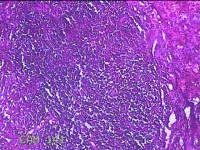

性别

男

年龄

32岁

临床诊断

1.急性化脓性阑尾炎并穿孔 2.弥漫性腹膜炎

一般病史

转移性右下腹疼痛1天。

标本名称

阑尾

大体所见

灰白暗红色阑尾4.8x1.3x0.7cm一条,表面糜烂,肿胀,带少许系膜,切断阑尾,见腔内暗红色。